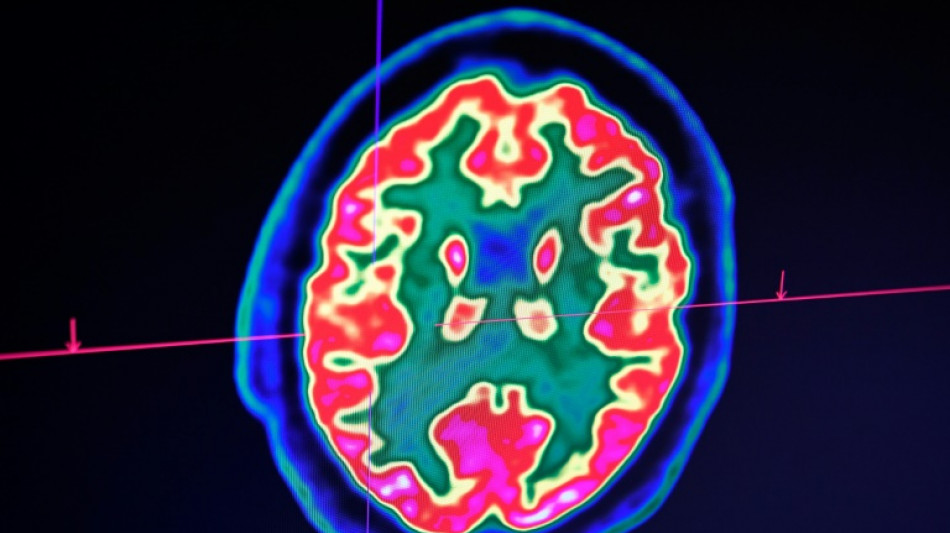

Sclérose en plaques: la découverte d'un lien avec un virus fait espérer une meilleure riposte / Photo: Fred TANNEAU - AFP/Archives